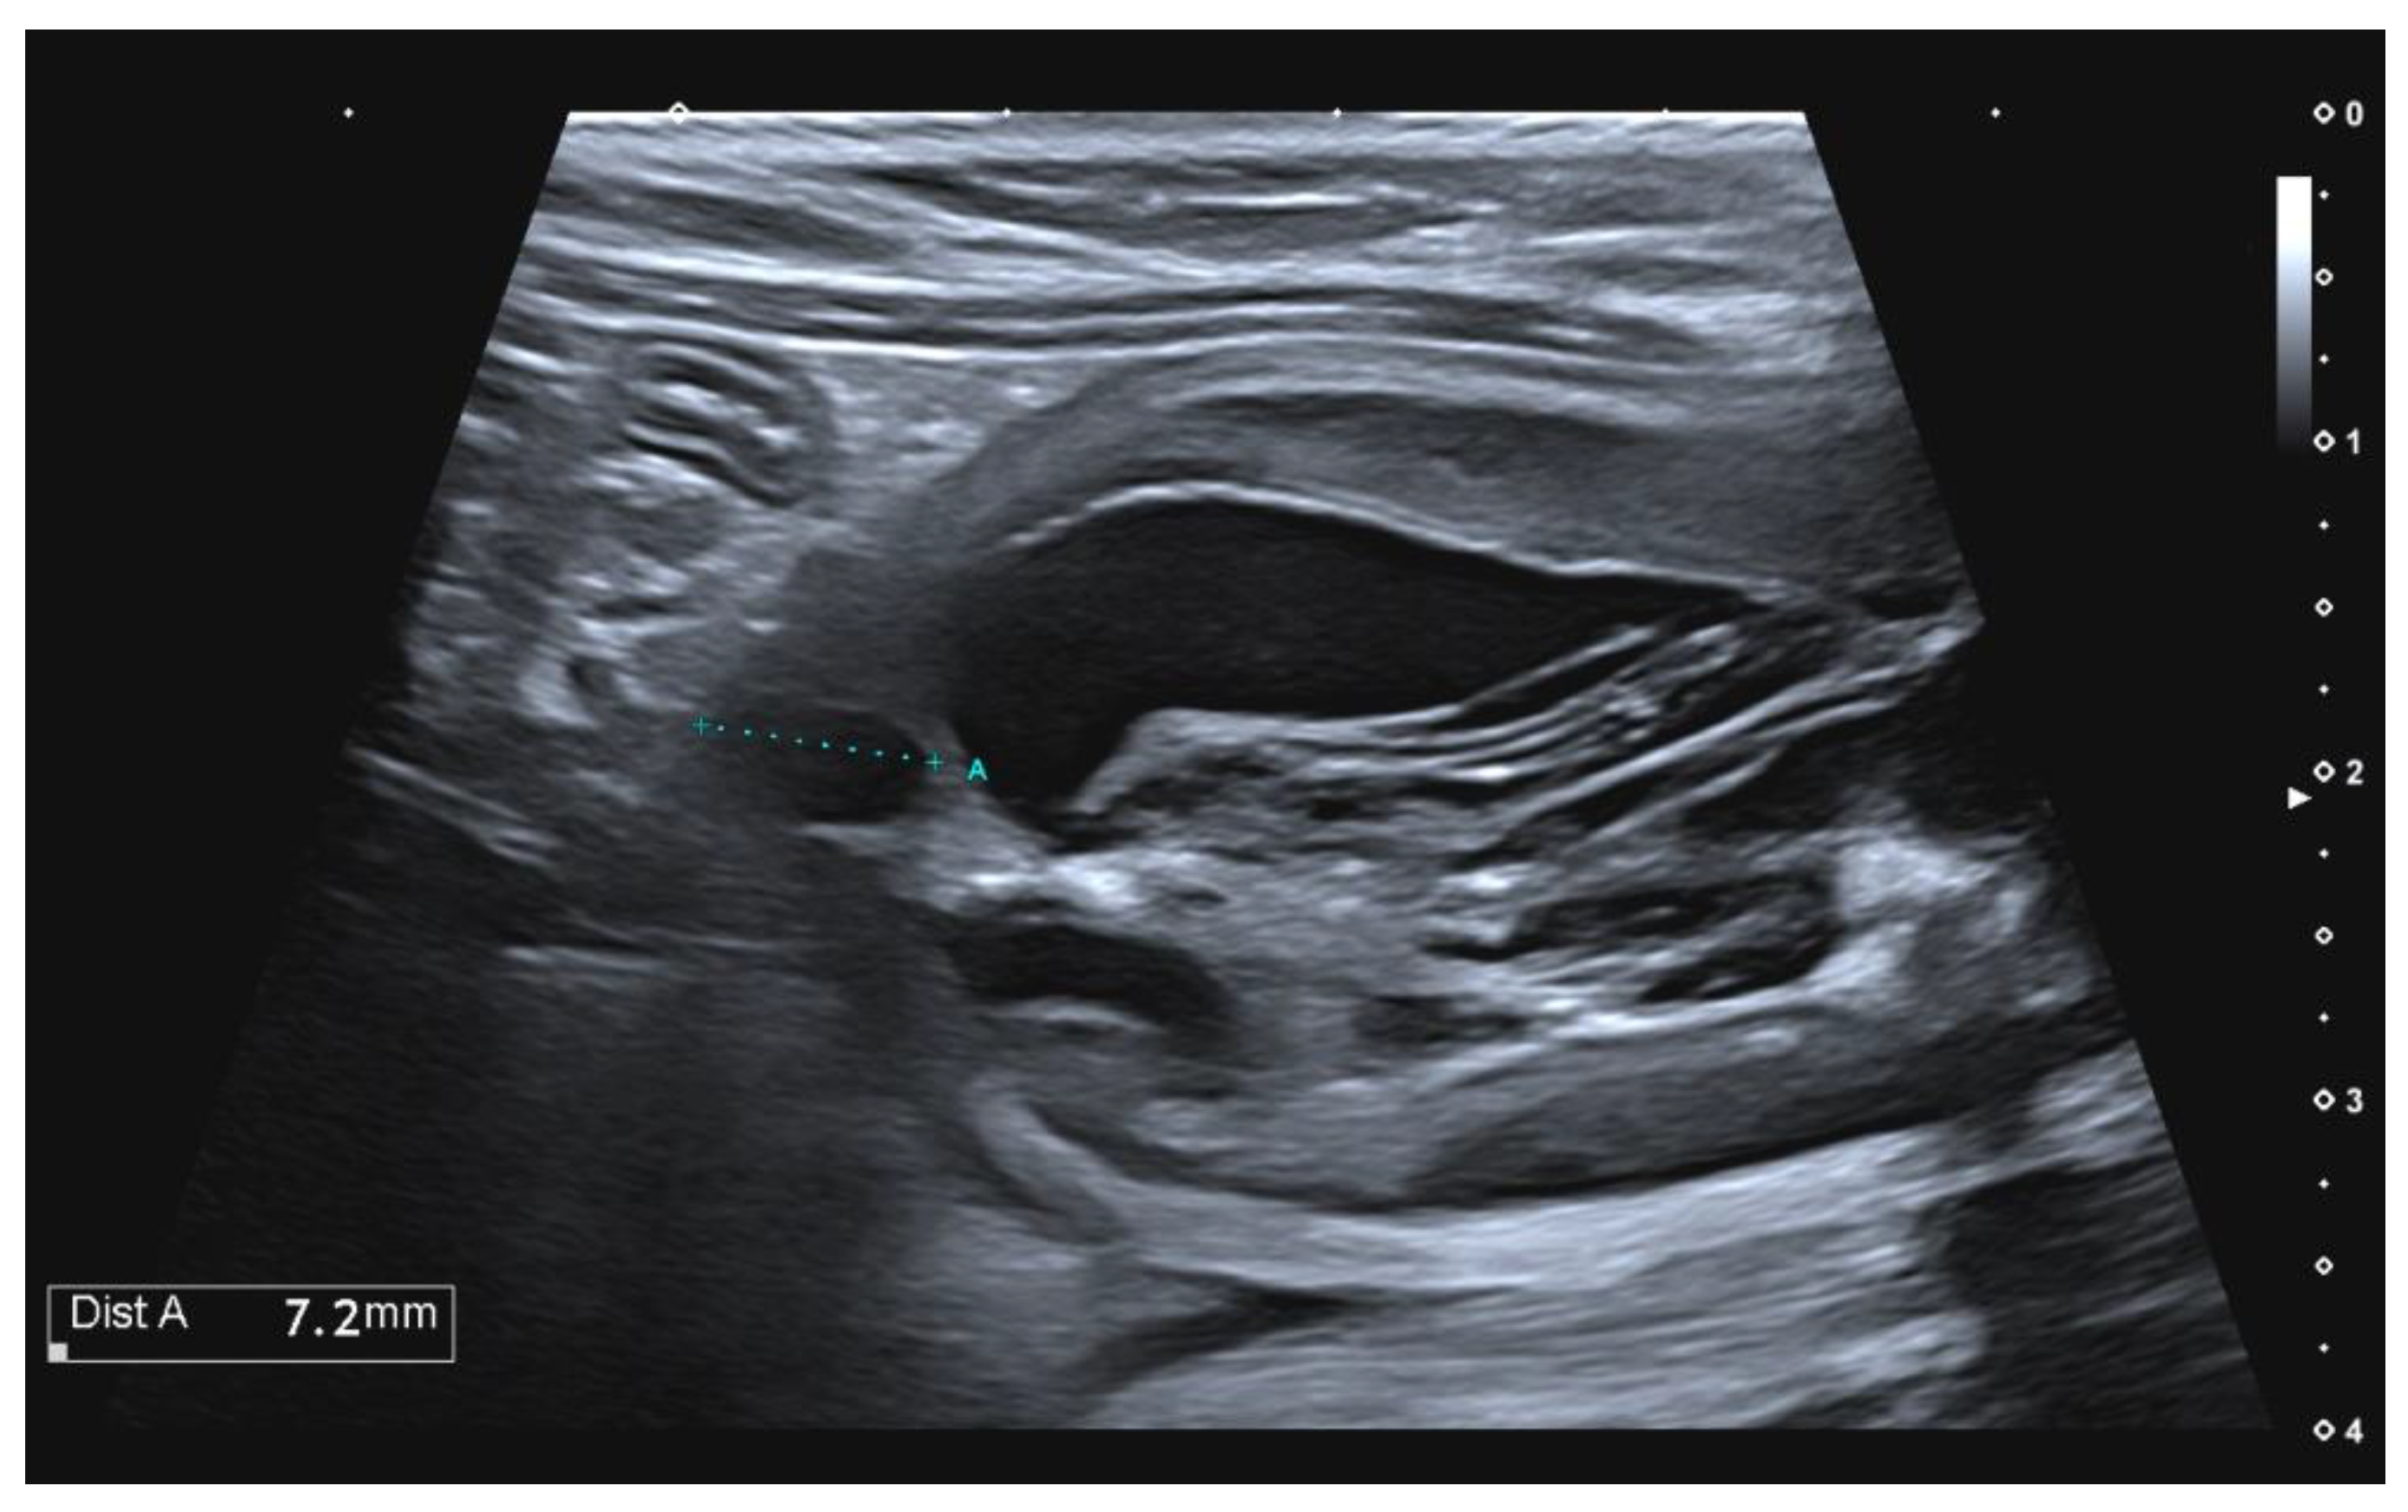

Pseudomembranous Cystitis An Uncommon Ultrasound Appearance of Cystitis in Cats and Dogs